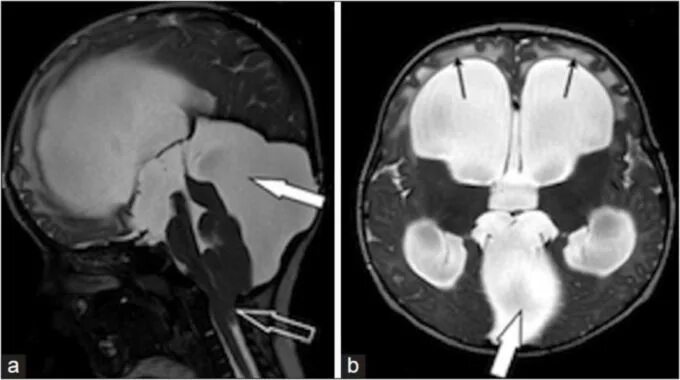

Ретроцеребеллярная ликворная киста